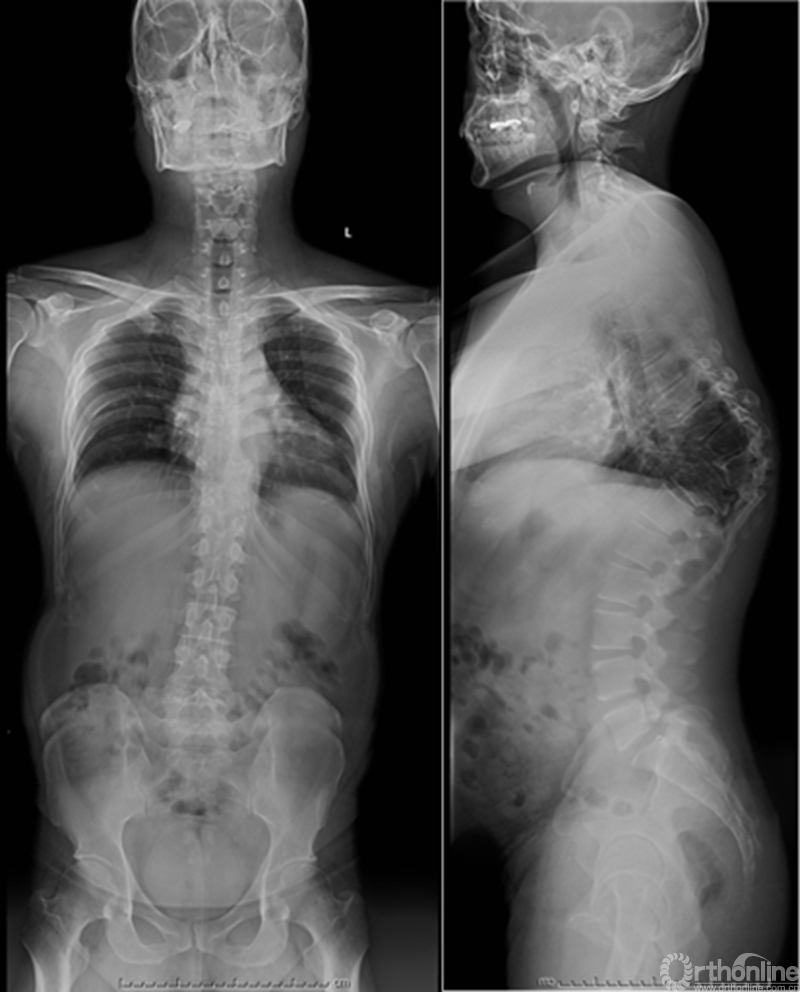

众所周知,脊椎结核后突畸形是结核病严重的后遗症之一。不仅影响患者外表仪容和心理,还可能出现晚发病灶造成截瘫。30多岁的小李就是一位脊柱结核后造成后凸畸形伴截瘫的患者,其畸形角度高达90度。针对此类患者的治疗大多就是截骨矫形,手术创伤大不说,椎体切除后造成的脊柱失稳等一系列后遗症也是令医生和患者担忧的。为解决临床上的这类问题,丁文元教授对传统的PVCR截骨技术进行了简化和改良,即后路单侧截骨部分椎体切除固定矫形术(UPVCR)入路,该技术采用后方单侧截骨,切除部分椎体、相邻椎间盘大部,保留对侧椎弓根及部分椎体,重建置入钛网支撑。随后,丁文元教授通过UPVCR技术对小李实施了手术,经过家人悉心地照顾,小李术后肌力恢复的良好,很快就出院了。三个月复查时竟是自己走路来的,临床疗效让患者及家人很是满意。

患者术前资料